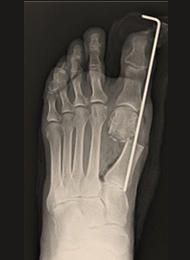

外反母趾

外反母趾とは、足の親指(母趾)が、第2趾の方へ曲がって変形している足の変形です。母趾の付け根の内側の痛みを生じる場合が多く、バニオンと呼ばれる胼胝(たこ)を形成することもあります。親指の症状だけでなく、第2趾や第3趾の足底痛や足の甲の痛みを生じることもあります。靴の調整や足底挿板による治療が基本となりますが、変形の矯正のためには母趾の中足骨を骨切りする手術が必要になる場合があります。

外反母趾の手術法は100種類以上あるといわれていますが、当院では患者さんへの侵襲の少ないDLMO(デルモ)法という第1中足骨遠位骨切り術を行っています。この術式は約2cmの皮膚切開で、第1中足骨を骨頭基部で骨切りしたのち、骨片間を鋼線1本で止めるというシンプルな術式です。この鋼線は手術後1か月で抜去するので、術後に体の中にインプラント(金属)が残らないこともこの術式の特徴といえます。

当院は、DLMO法の第1人者である須田康文医師のもとで研修を積んだ竹島憲一郎医師が執刀を担当しており、多くの患者さんの治療を行っています。

![]() 術前 |

![]() 術直後 |

![]() 術後1年 |